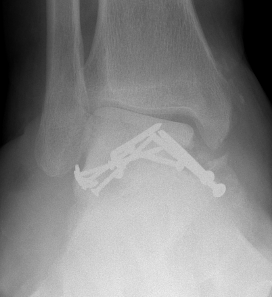

BlairblairAnkle Blair Fusion LateralAnkle Blair Fusion AP